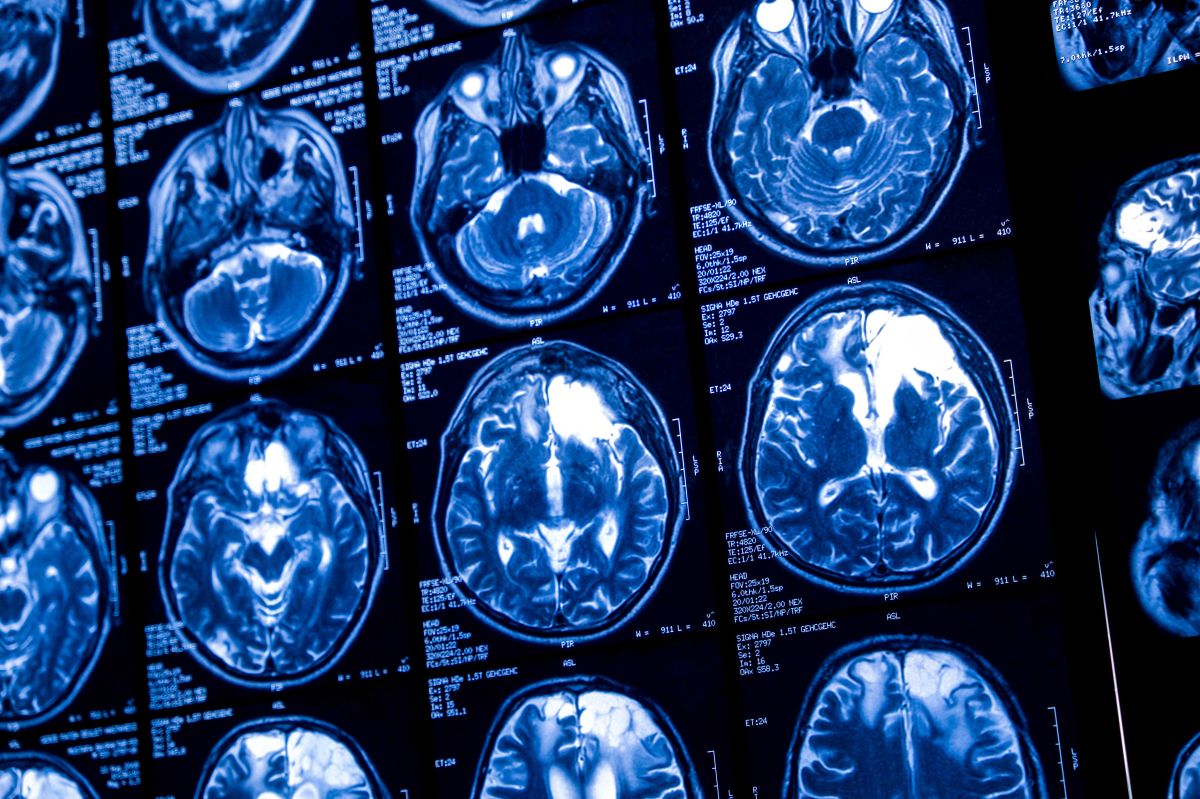

VALÈNCIA (Servimedia). En la LXXVI Reunión Anual de la Sociedad Española de Neurología (SEN) se ha presentado el ‘Informe sobre la relación entre las enfermedades neurológicas y la salud cerebral’, elaborado por la SEN con la colaboración de Angelini Pharma. El documento destaca que el 20% de las personas con epilepsia desarrollan ansiedad y el 23% depresión, complicaciones que agravan el impacto emocional de la enfermedad y que afectan a la eficacia de los tratamientos y la calidad de vida de los pacientes.

Más de 50 millones de personas a nivel mundial y 400.000 en España padecen la epilepsia, situándola como una de las enfermedades neurológicas más comunes. A pesar de su alta prevalencia, sigue siendo una de las patologías más desconocidas y estigmatizadas. Según la Organización Mundial de la Salud (OMS), los pacientes con esta enfermedad tienen un riesgo de mortalidad prematura tres veces mayor que el de la población general debido a la dificultad para controlar las crisis, los efectos secundarios de los tratamientos y una mayor exposición a accidentes y complicaciones secundarias.

El informe defiende un modelo de atención bio-psico-social, avalado por OMS, que aborde la enfermedad desde una perspectiva integral y señala la efectividad de combinar tratamientos médicos con intervenciones psicosociales. También resalta la importancia de hábitos saludables, como una dieta equilibrada, ejercicio físico, un buen descanso y evitar el consumo de alcohol y tabaco, para reducir la frecuencia de las crisis y mejorar la calidad de vida.